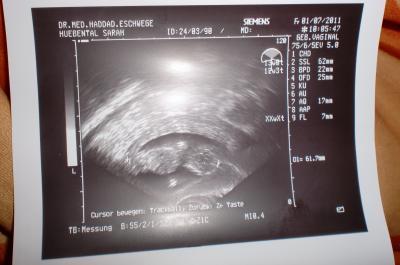

war letzte woche fr bei FA...war da 13 woche....jetzte 14 woche...=) Würmchen wächst wie irre...=)mein freund konnte es kaum glauben.... abba echt wahnsinn wie schnell der wurm wachsen tut=) noch ein schööönes bildchen dabei=)

Bild zu lieber zu späääd als nie..=) - Forum für Januar - Mamis